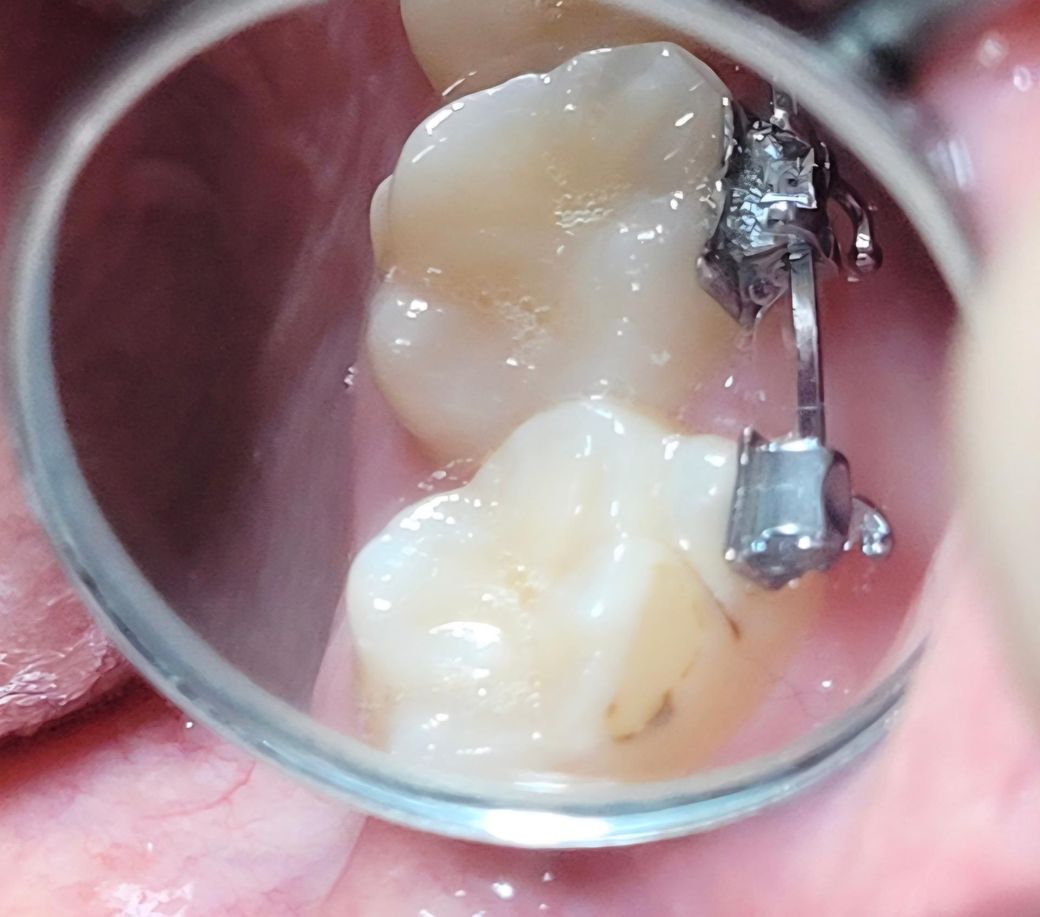

2번사진 25년 11월

• 2번 째 사진